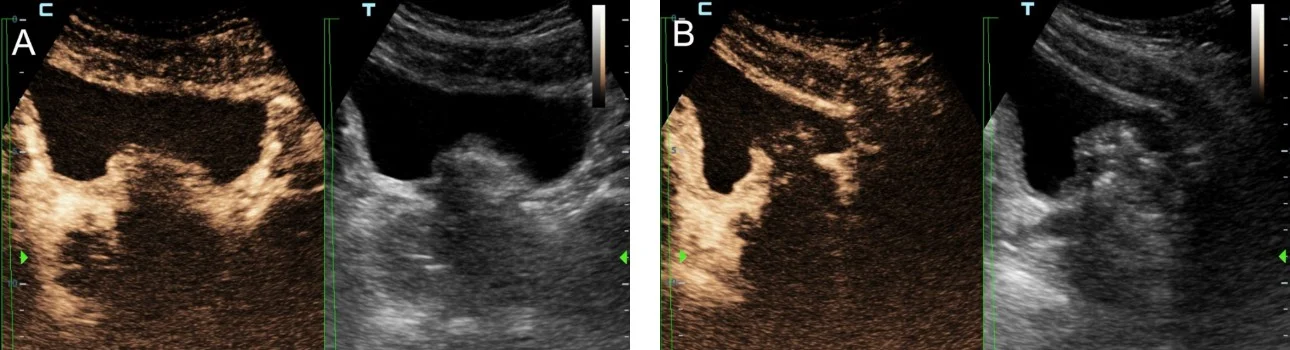

In addition to the aforementioned morphologic evaluation, contrast-enhanced US (CEUS) with intravenous administration of a second-generation echo-enhancer (SonoVue, Bracco, Milan, Italy) can be applied to study the hemodynamic and perfusional changes that occur in the prostate post PAE [3,4]. Prostatic infarcts can be easily detected as enhancement defects immediately post PAE (Fig 1); they are considered as a reliable sign of the local efficacy of PAE and they also correlate with clinical success.

Figure1: Representative transabdominal US and CEUS images of the prostate pre and post PAE. Images are shown in a ‘split-screen’ mode with unenhanced, reference B-mode image on the left, and the corresponding CEUS image on the right. A: At baseline, almost homogeneous enhancement of the entire gland is noted. B: One day post PAE, extensive irregular echogenicities are detected by US in both prostatic lobes. The echogenicities are also partially present in the CEUS image, which additionally shows lack of enhancement (infarction) in the largest part of the prostate. C: One month post PAE, US shows almost complete disappearance of the echogenicities and reduction in prostate size. CEUS shows persistent lack of enhancement in the largest part of the prostate.